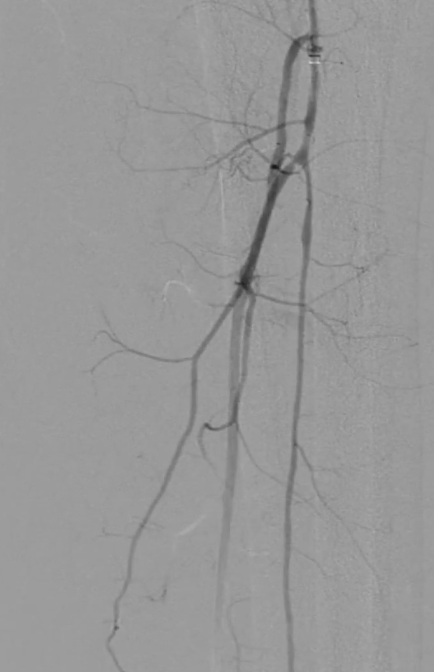

栓塞处理:造影发现管腔获得尚可,但是流速明显较慢,考虑保护伞上方管腔闭塞(考虑斑块/血栓脱落),用6F导管反复抽吸后收回保护伞。

夹层发现及处理:

更换V18导丝后造影显示,胫后动脉血流通畅,胫前动脉疑似仍有小的血栓脱落,导致栓塞。

股浅动脉全程管腔获得尚可,但中段有明显的夹层形成,

先用5mm长球囊充分预扩张;再次造影显示,股浅动脉近中段管腔获得良好,中远段仍有大量的夹层

采用药物涂层球囊(DCB)对股浅动脉病变段全程覆盖:近端用5-250新型药涂球囊,远端用5-150 impact 药涂球囊;

造影显示中段仍有局限性夹层,为保证远期通畅率,植入补救性支架并以5mm球囊后扩张